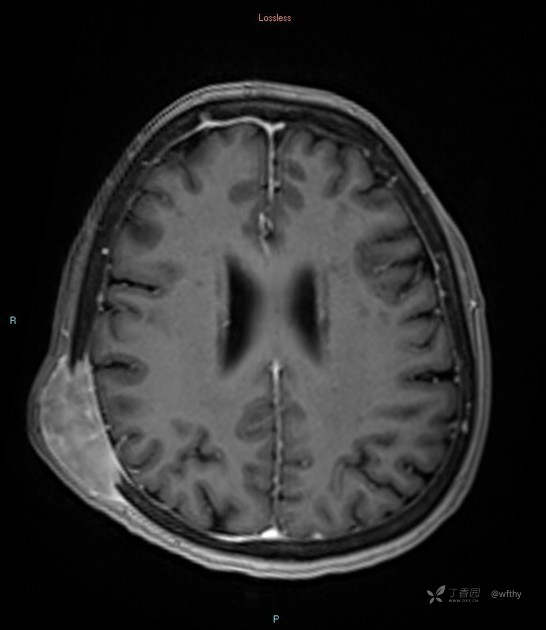

病例女65,头部肿块